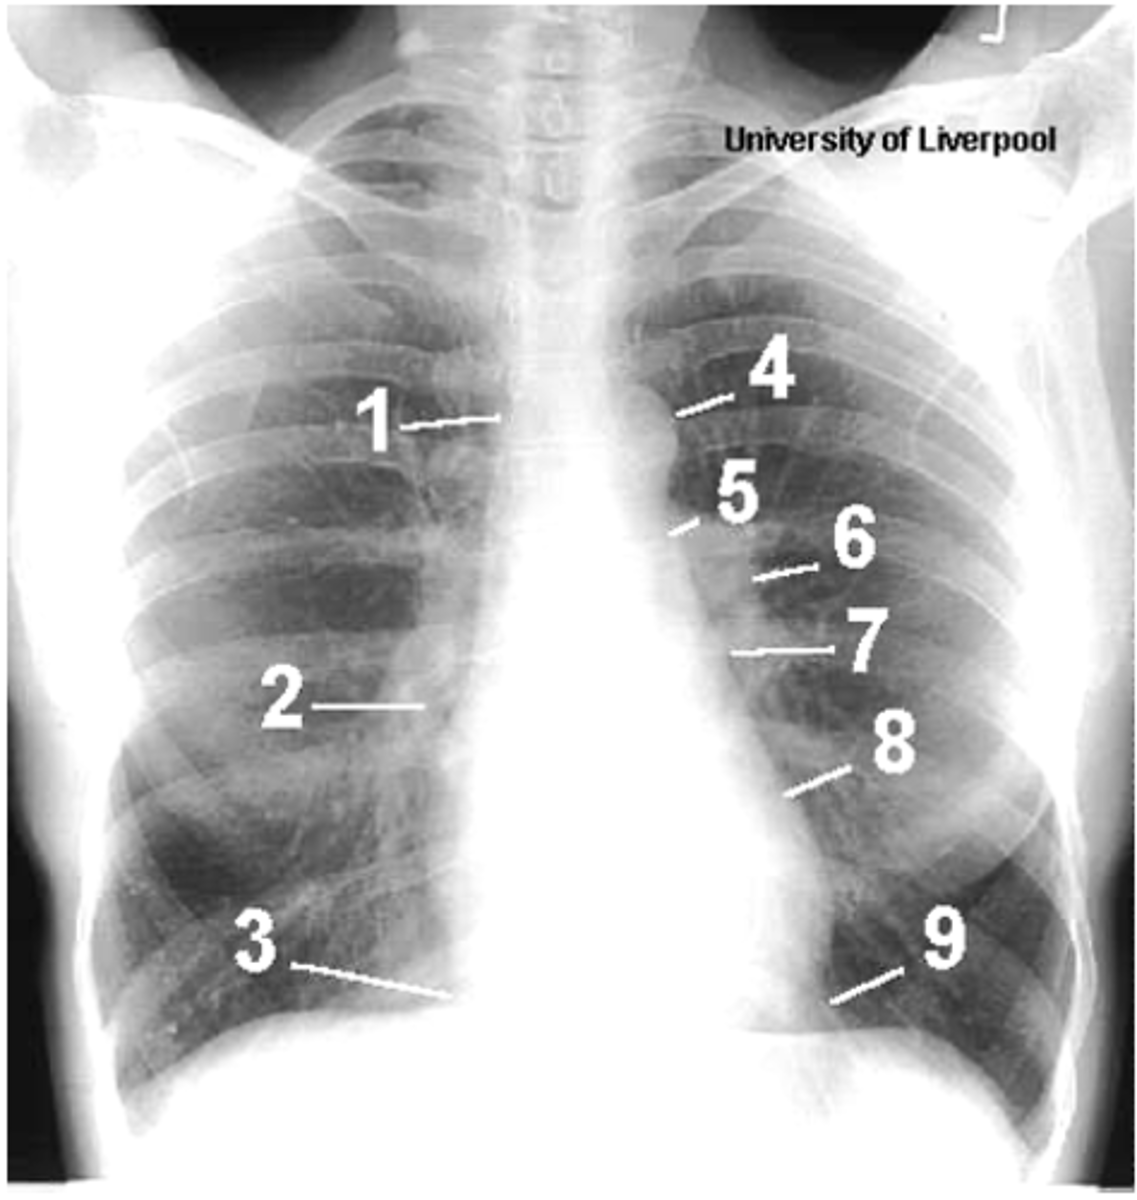

1

ID structures

1- superior vena cava

2- right atrium

3- inferior vena cava

4- aortic arch or knob

5- left pulmonary trunk

6- left pulmonary artery

7- left atrium

8- left ventricle

9- left cardiophrenic angle

<p>1- superior vena cava</p><p>2- right atrium</p><p>3- inferior vena cava</p><p>4- aortic arch or knob</p><p>5- left pulmonary trunk</p><p>6- left pulmonary artery</p><p>7- left atrium</p><p>8- left ventricle</p><p>9- left cardiophrenic angle</p>